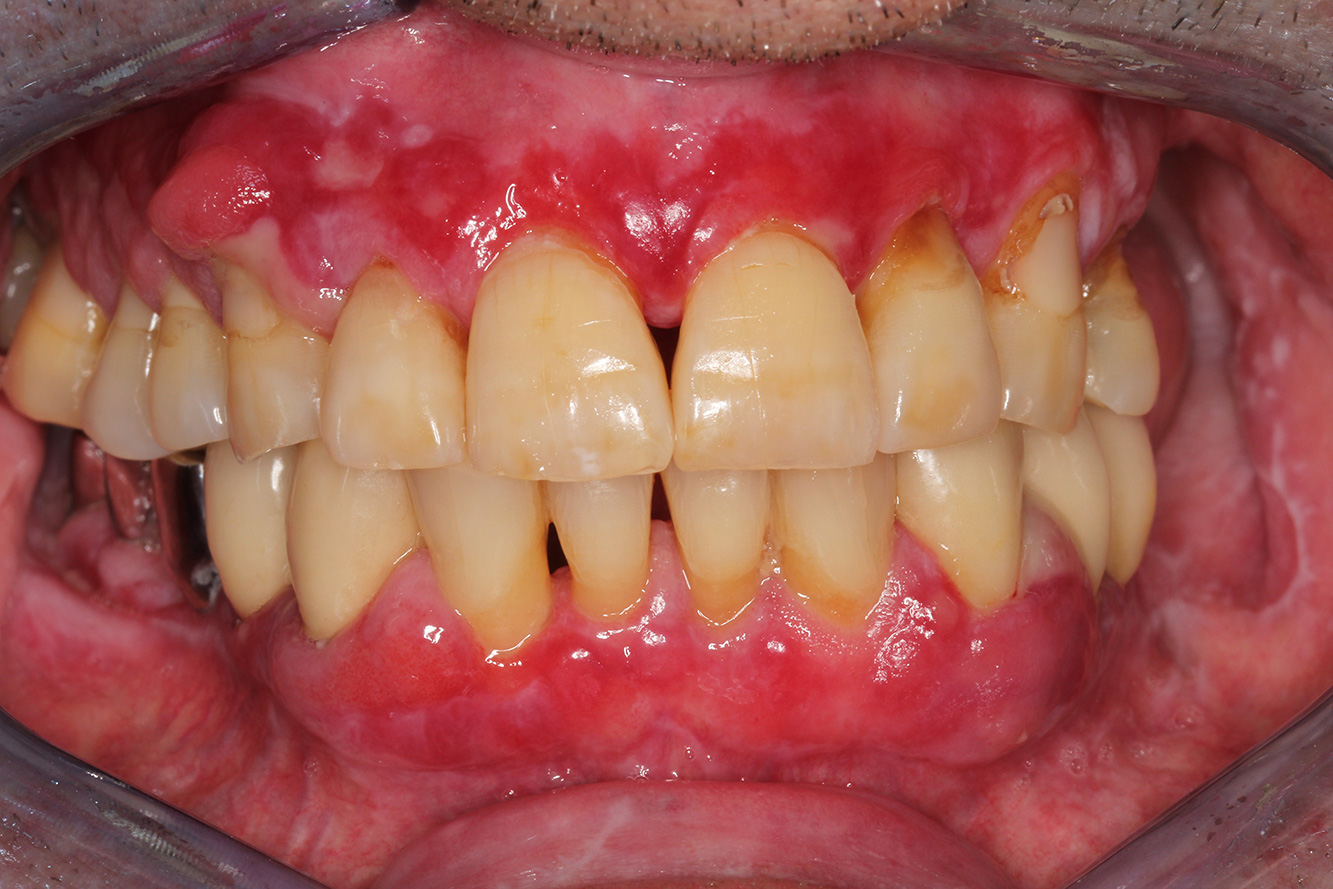

The Diabetic Patient with Pre-Existing Periodontitis

This case report of a 52-year-old male with type 2 diabetes and periodontitis emphasizes personalized preventive measures and periodontal health maintenance to manage the moderate disease progression risk. more

The 28-Year-Old Cigarette Smoker with Dental Erosions

28-year-old patient, smoker, with erosions. The bidirectional relationship between oral and general medical health is very well known. It is no longer sufficient – and arguably even old-fashioned – to consider intraoral conditions in isolation. In order to create a personalized, case-specific preventive and patient profile, it is essential to take a detailed medical history and perform diligent examination of the general medical and intraoral health, as well as considering the two in combination. more